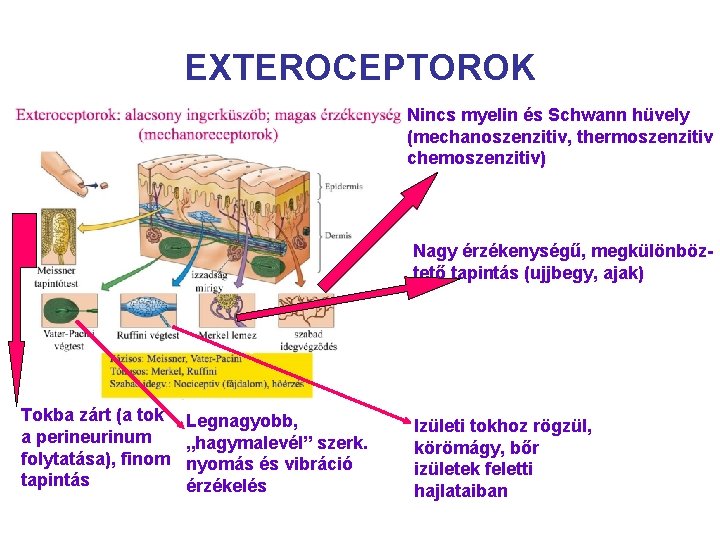

EXTEROCEPTOROK A KÜLSŐ KÖRNYEZET INFORMÁCIÓIT ÉRZÉKELIK: Hő, fájdalom, tapintás mechanoreceptor thermoreceptor nociceptor

EXTEROCEPTOROK Nincs myelin és Schwann hüvely (mechanoszenzitiv, thermoszenzitiv chemoszenzitiv) Nagy érzékenységű, megkülönböztető tapintás (ujjbegy, ajak) Tokba zárt (a tok a perineurinum folytatása), finom tapintás Legnagyobb, „hagymalevél” szerk. nyomás és vibráció érzékelés Izületi tokhoz rögzül, körömágy, bőr izületek feletti hajlataiban